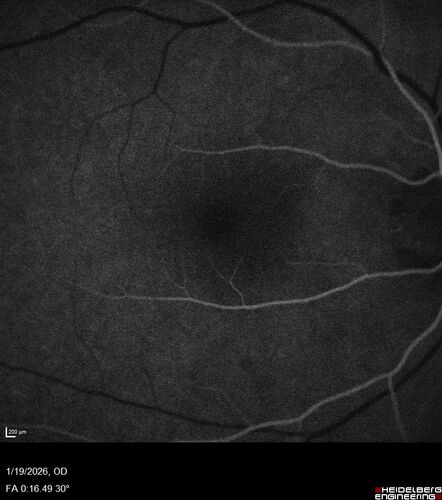

Acute Retinal Pigment Epitheliitis (Krills disease)

15 year old with sudden central vision loss in one eye. The vision loss persisted though for at least 6 months (which may be a laser injury)